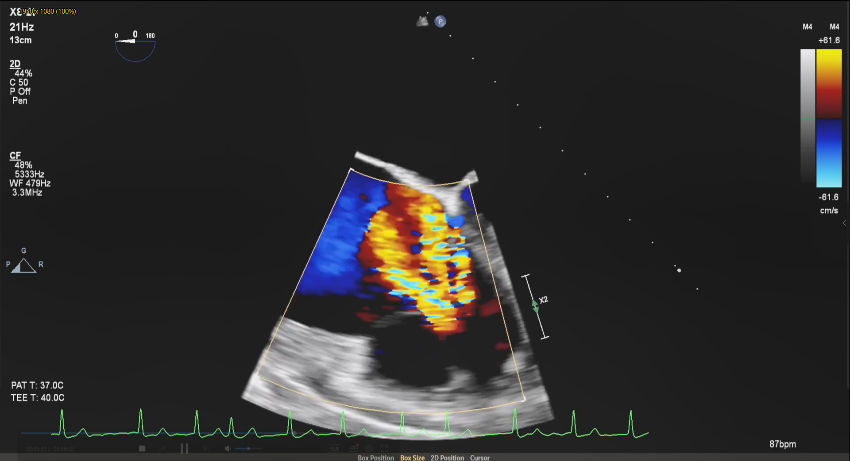

全麻下经右颈静脉入路,在食道超声及放射线引导下,将三尖瓣导丝输送导管经三尖瓣指引导管送至右心室,定位三尖瓣瓣环穿刺位点。穿越导丝连接高频发生器穿刺三尖瓣环(图2),在三尖瓣瓣环上植入一对锚片。通过缩短两个锚片之间的距离折叠三尖瓣瓣环,并通过3D-TEE、2D-TEE确认瓣环折叠及三尖瓣反流情况,最终实现三尖瓣瓣环的二瓣叶化(视频1),从而降低因瓣环扩大、瓣叶关闭不全产生的三尖瓣反流。

图2 :穿越导丝穿刺三尖瓣环(a:2D-TEE,b:3D-TEE)